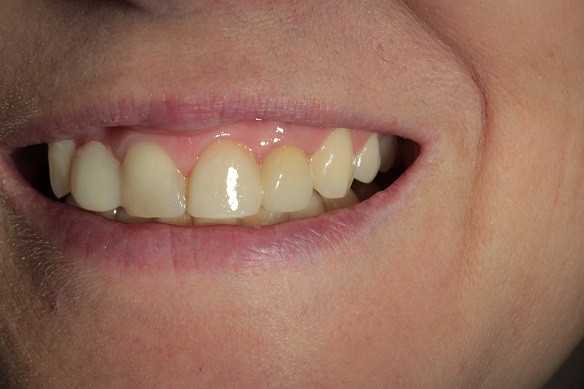

На странице представлено портфолио стоматологий Новосибирска с фото работ до и после имплантации зубов. Мы собрали разные клинические случаи: одиночные импланты, восстановление нескольких зубов и полная реконструкция зубного ряда. Здесь вы можете видеть, как выглядят восстановленные зубы, меняется форма улыбки после процедуры. Изучите результаты до и после имплантации зубов, чтобы оценить качество работы врачей и выбрать стоматологию в Новосибирске, которая поможет вернуть функциональность и эстетику вашей улыбке.

Тотальное протезирование верхней челюсти металлокерамическими коронками с опорой на имплантаты Astra-Tech (Швеция) с левой стороны, и на свои зубы с правой стороны

Тотальное протезирование верхней челюсти на 6 имплантатах Astra-Tech (Швеция)